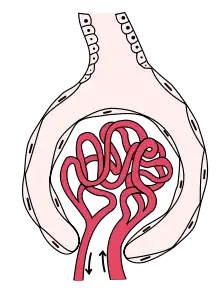

Glomerulonephritis (GN) is a term used to refer to several kidney diseases (usually affecting both kidneys). Many of the diseases are characterised by inflammation either of the glomeruli or of the small blood vessels in the kidneys, hence the name,[1] but not all diseases necessarily have an inflammatory component.

Glomerulonephritis refers to an inflammation of the glomerulus, which is the unit involved in filtration in the kidney. This inflammation typically results in one or both of the nephrotic or nephritic syndromes.[2]: 500